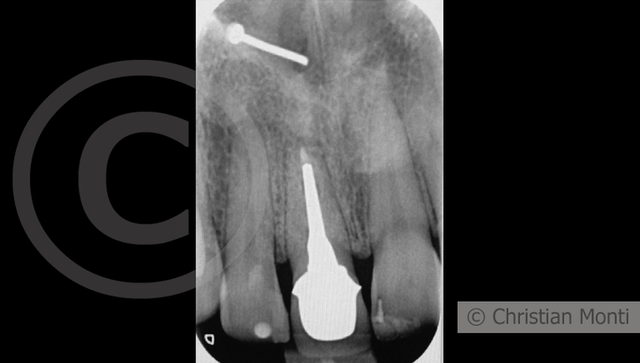

EDENTULIA SINGOLA

Impianto in sostituzione di un incisivo superiore